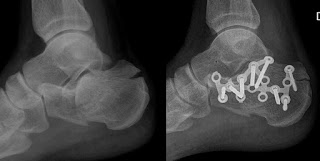

Hoy para comenzar os propongo una interesante revisión realizada por nuestros compañeros de FREMAP sobre las alternativas quirúrgicas en el tratamiento de las fracturas intraarticulares del calcáneo.